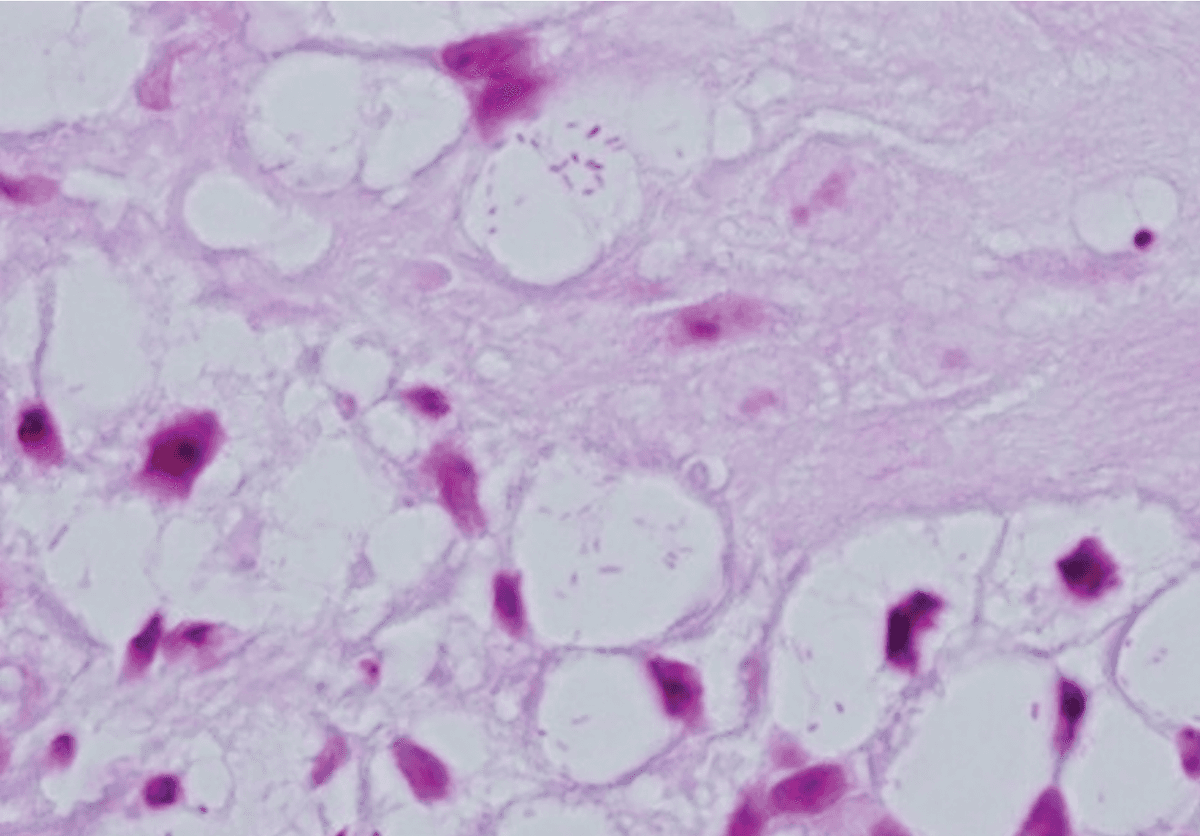

Computed tomography of the face demonstrates soft tissue masses involving the nasal cavity and nasopharynx with focal erosion of adjacent bone, without abscess formation. A biopsy of the nasal lesion is performed and shown below. Histopathology reveals granulomatous inflammation with numerous foamy macrophages containing intracellular Gram-negative bacilli (Mikulicz cells).

Left: Gram stain showing intracellular Gram-negative bacilli within Mikulicz cells. Right: Steiner staining highlights the bacilli within the cytoplasm of the Mikulicz cells.

Histopathology is central to diagnosis and classically demonstrates granulomatous inflammation with foamy macrophages—known as Mikulicz cells—containing intracellular Gram-negative bacilli. Although the organism can be cultured on standard laboratory media, biopsy is often required for definitive diagnosis.